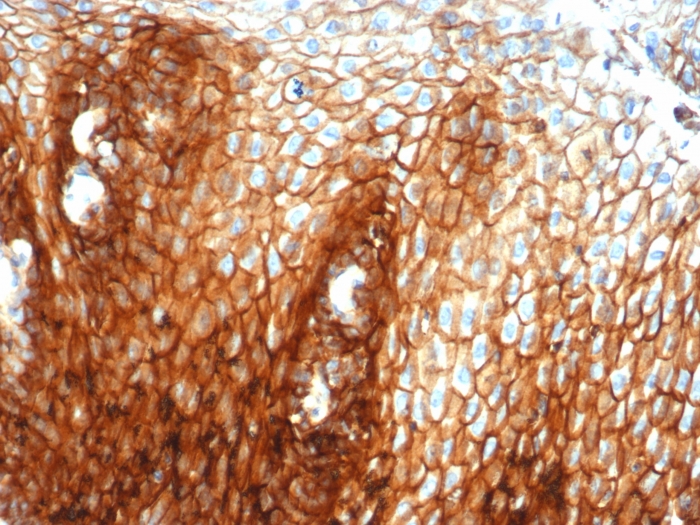

Formalin-fixed, paraffin-embedded human esophagus stained with CD44 Recombinant Rabbit Monoclonal Antibody (HCAM/6459R).